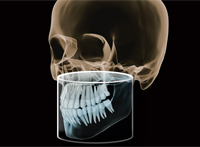

3D комп'ютерна томографія

Дентальна комп’ютерна томографія (КТ) — це діагностична процедура в сучасній стоматології. Її результат дозволяє терапевту достовірно оцінити стан та анатомічні особливості кореневих каналів, локалізувати запальний процес. Ортопед може побачити точне розташування, будову СНЩС, імплантолог — оцінити параметри щелепної кістки, структуру, щільність та об’єм.

3D знімок — точний метод діагностики, лікар отримує повну інформацію про стан щелепно-лицьового апарату пацієнта, гайморових пазух. Отримані в результаті сканування знімки дають можливість стоматологу збільшувати, повертати і досліджувати під кутом області, що цікавлять, що неможливо при рентген-дослідженні. Також комп’ютерна томографія вимірює висоту, ширину кістки, визначає тип. Це потрібно, щоб підібрати розмір та тип імплантату при плануванні операції.

Для виконання 3D знімка пацієнта просять закусити зубами спеціальну закусочну пластину і зафіксувати положення за допомогою фіксуючої опори. Протягом 15-30 секунд слід дотримуватися нерухомості.

ORTHOPHOS SL 3D. Довершена рентгенівська система для будь якої практики.

ORTHOPHOS S 3D це прилад з всеохоплюючими можливостями. Починаючи з надчітких панорамних 2D знімків завдяки сучасному DCS сенсору і аж до максимальної гнучкості у виборі 3D обєму зйомки (11Х10, 8Х8, 5Х5). У коплексі з програмним забезпеченням SIDEXIS 4 відкриє нові можливості для Вашої практики.

Поле огляду 8 см х 8 см (VOL1) дозволяє відобразити всю щелепу пацієнта на одному знімку, що спрощує діагностику та планування лікування. При ендодонтичному лікуванні достатньо меншого обєму 5смХ5,5см (VOL2). Таким чином ми не тільки зменшуємо дозу опромінення а й скорочуємо час на постановку діагнозу. В режимі HD (висока роздільна здатність, 500 знімків зо один оборот ) при VOL2 з розміром вокселя 100 мкм Ви отримаєте надчіткі знімки для ендодонтичного лікування. Обєм 11 см Х 10 см надасть Вам максимум потрібної інформації.